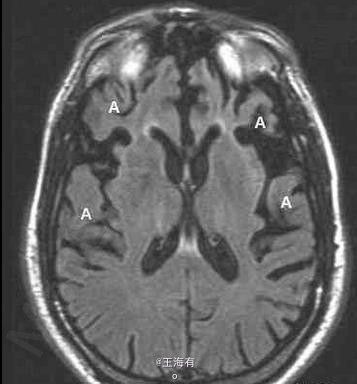

49岁,男,进行性行为改变入院

进行性智能减退,记忆障碍明显

Pick病 处理 此病暂无有效疗法

Pick病是一种罕见的进行性变性疾病,大多累及额叶和颞叶。预后本病预后不良。常在发病1年内迅速转入痴呆